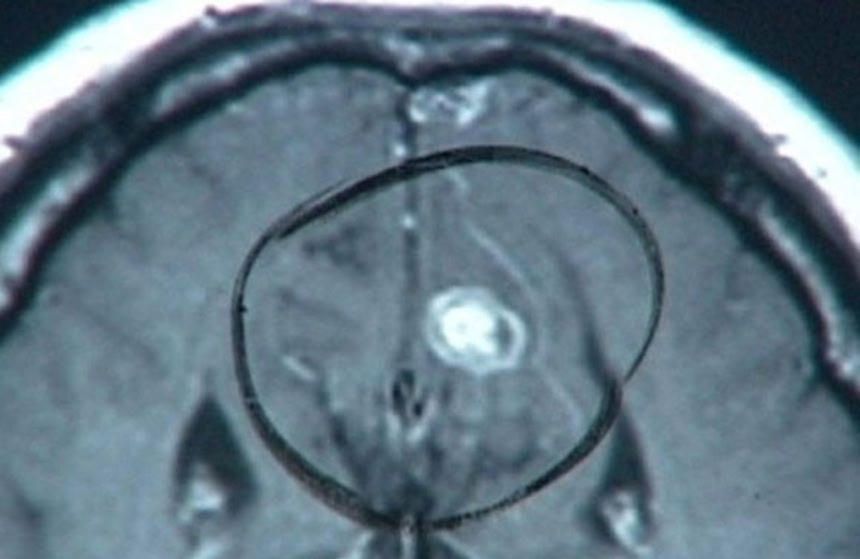

ホイットマンの予感は正しかったようだ。脳神経学者のデイヴィッド・イーグルマンが著作『Incognito: The Secret Lives of the Brain』の中で詳しく述べているが、検死解剖の結果、ホイットマンの脳の視床と呼ばれる部分に10セント大の腫瘍がひとつ見つかった。

それが恐怖や怒りを統制する役割を担う扁桃体を圧迫していていたのだ。ホイットマンが豹変してしまった原因のひとつに、この小さな腫瘍があることは間違いないだろう。彼の心の理性的な思考部分をむしばみ、死へと追いやってしまったようだ。